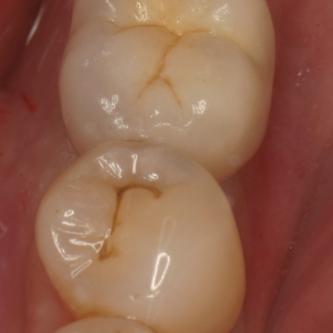

Exemple 2: Un implant remplaçant la racine d'une molaire inférieure gauche.

Exemple 2: La couronne en céramique scellée sur cet implant.